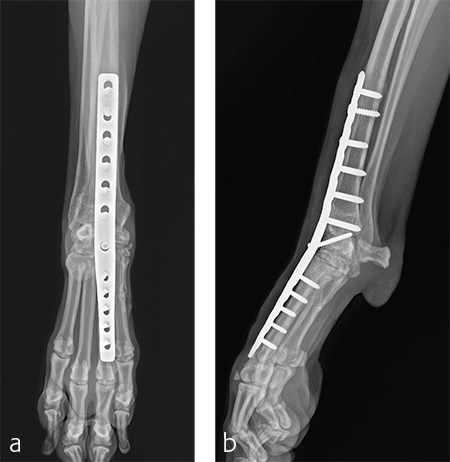

A custom fiberglass palmar splint was applied from the paw to just distal to the elbow after surgery. The splint was used for 4 weeks followed by a soft padded bandage for 4 weeks. Bandage changes were performed weekly. Activity was restricted to leash walks only for 12 weeks postoperatively. Radiographic examination 8 weeks after surgery revealed early healing of the pancarpal arthrodesis and stable implants. No complications were noted (Fig 6).

The patient was returned to normal activity 4 months after surgery. Radiographic examinations at 6 and 6.5 months after surgery revealed stable implants and fusion of the carpus (Fig 7 and 8). Functional outcome was excellent 1 year postoperatively. The patient had returned to full weight-bearing without lameness and the carpus was pain-free and stable.